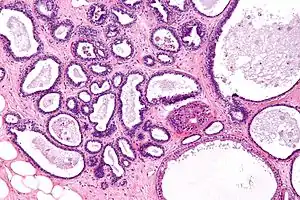

| Micrograph showing fibrocystic breast changes. H&E stain. | |